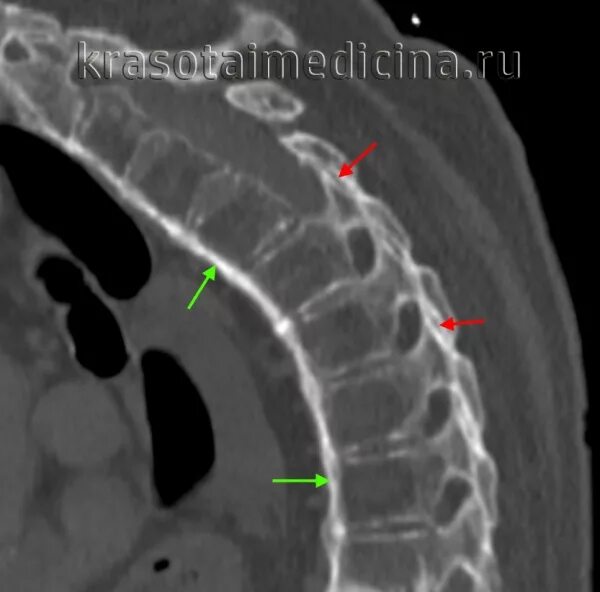

Заболевание кт